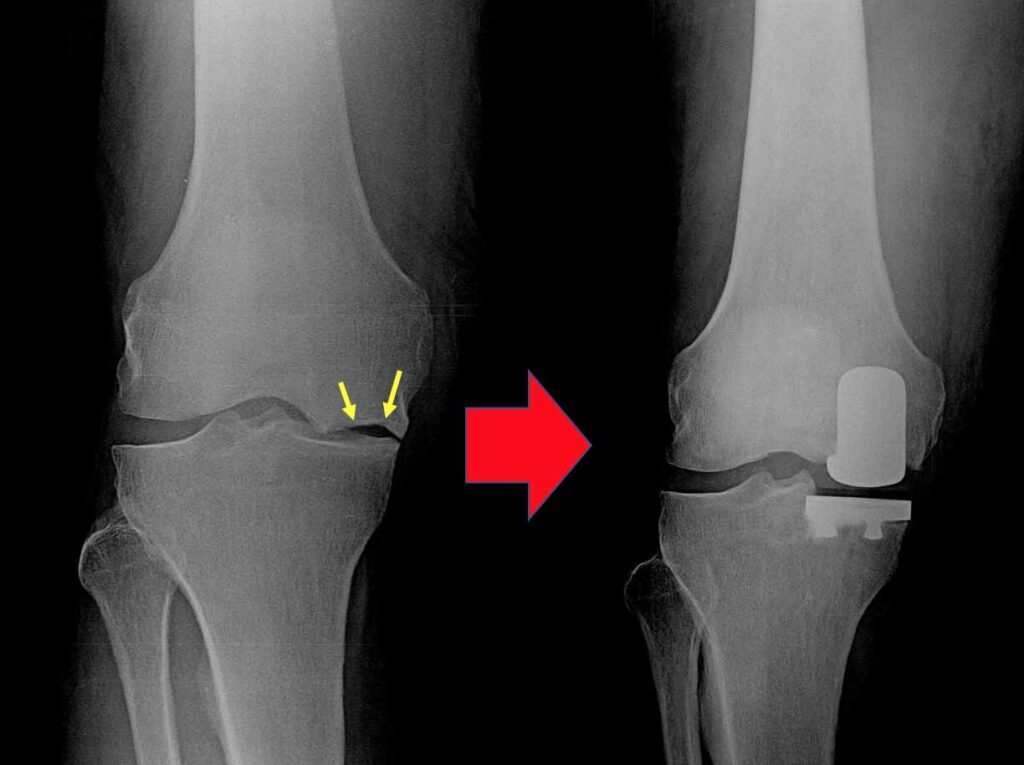

Partial knee replacement (PKR), also known as unicondylar or unicompartmental knee replacement, is a surgical procedure that replaces only the damaged portion of the knee joint, while preserving the healthy parts. Unlike total knee replacement, PKR focuses on restoring function by targeting one or two specific compartments of the knee.